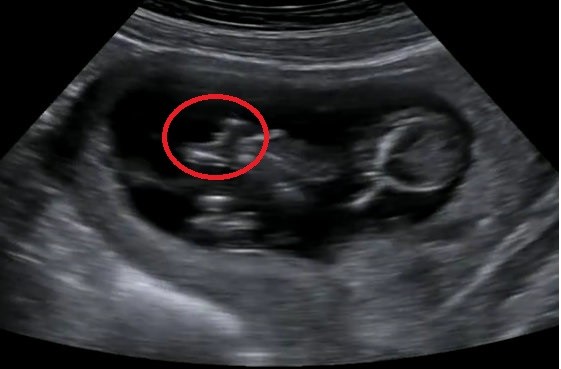

Jest to dla mnie szok ze w 1 cyklu mogą się zrobić 4 nie wiem z czego. Zawsze mi się wydawało ze krwotoczna robi się z ciałka żółtego lub z pęcherzyka. ...... tak mi tłumaczyli wiec nie rozumiem skąd są 4 :errr: Ja też mam teraz 1 krwotoczna 3.5 cm endometrialna 2.6 chyba. Ona teraz na tej kontroli w trakcie antyków ma nadzieję że ich nie będzie i zrobi Ci start jak znikną a jak nie to przedłuży antyki. Mi pomaga naproxen i maść z niedźwiedzia na plecy i rozchodzic

Jakie duże te krwotoczne. ?

Chyba cos ok 3 cm ale glowy nie dam, nie pamiętam. Za dlugi dzien dziś. Jeszcze wieczorem bylam na usg piersi.Kurde od paru dni tak mnie bola ze masakra. Nawet koszulka sprawia ból :( mam po jednej torbieli w kazdej piersi ale malutkie ok 1 cm.A bola przez te wszystkie hormony.